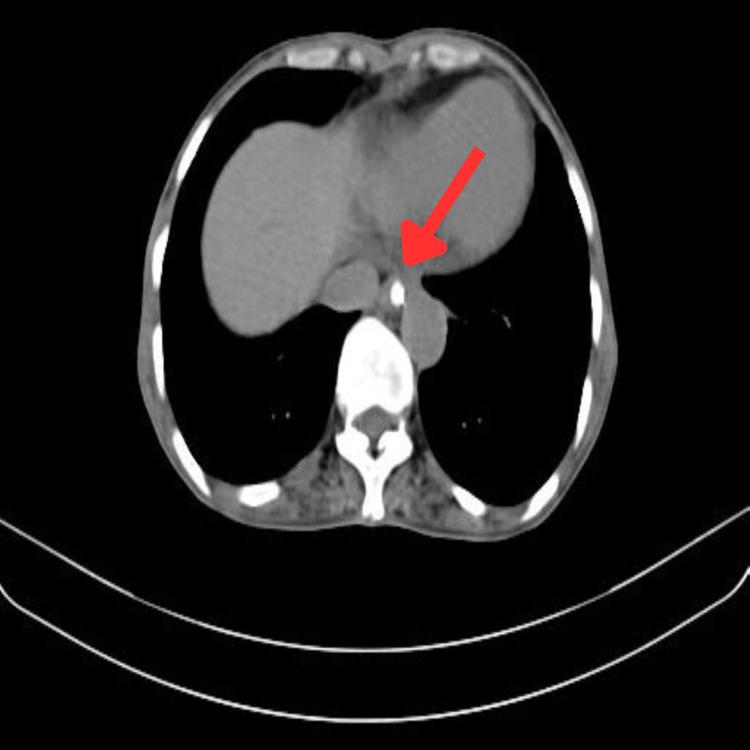

Esophageal cancer is a malignant epithelial alteration that takes place in the middle or upper part of the esophagus. Given the escalating population of individuals who have successfully overcome esophageal cancer, the significance of addressing disease- and treatment-associated complaints and symptoms is increasingly pertinent. This highlights the necessity of interventions meant to enhance quality of life (QOL). We present the case of a 60-year-old female diagnosed with esophageal squamous cell carcinoma who presented with chief complaints of generalized weakness, breathlessness, and nausea. Patient-tailored physiotherapy pre-rehabilitation and post-rehabilitation, including strengthening exercises, breathing exercises, dyspnea-relieving positions, Mendelsohn maneuver, Shaker exercise, among others, were administered. These interventions proved effective in enhancing the patient's functional independence and QOL. Treatment commenced one week prior to the first chemotherapy session. Post-chemotherapy intervention was provided, and on the day of discharge, follow-up revealed improved strength and QOL.

食管癌是一种发生在食管中上部的恶性上皮性病变。鉴于成功战胜食管癌的人数不断增加,解决与疾病和治疗相关的不适和症状的重要性日益凸显。这突出了旨在提高生活质量(QOL)的干预措施的必要性。我们报告一例60岁女性,诊断为食管鳞状细胞癌,主要症状为全身无力、呼吸急促和恶心。实施了针对患者的康复前和康复后物理治疗,包括强化锻炼、呼吸练习、缓解呼吸困难的体位、门德尔松手法、摇头运动等。这些干预措施被证明有效地提高了患者的功能独立性和生活质量。治疗在第一次化疗疗程前一周开始。提供了化疗后干预,出院当天的随访显示力量和生活质量有所改善。